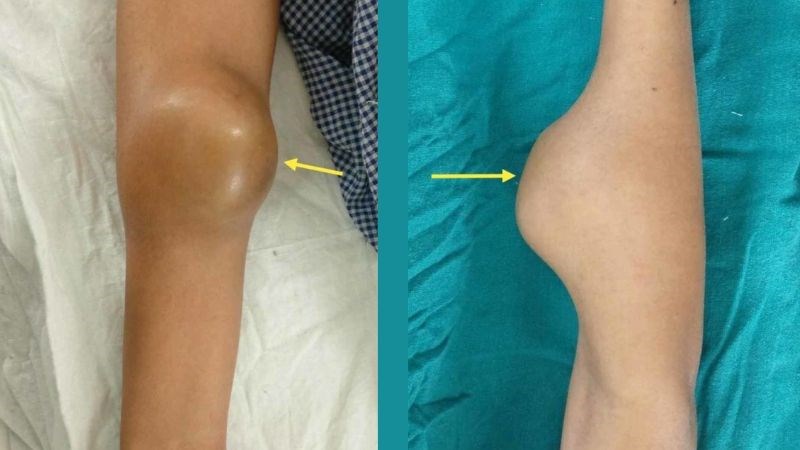

Nếu bạn đang bị đau xương, bác sĩ sẽ thăm khám các triệu chứng của bạn và kiểm tra khu vực bị ảnh hưởng trước khi quyết định xem bạn có cần thực hiện thêm bất kỳ xét nghiệm nào hay không.

Họ sẽ tìm bất kỳ vết sưng hoặc khối u nào và hỏi xem bạn có gặp khó khăn khi di chuyển vùng bị ảnh hưởng không. Họ cũng có thể hỏi về loại cơn đau mà bạn trải qua, đau liên tục hay đến rồi đi và liệu có điều gì làm cho cơn đau tồi tệ hơn không.

Sau khi được kiểm tra, bạn có thể được đề nghị chụp X-quang vùng bị ảnh hưởng để tìm kiếm bất kỳ vấn đề nào trong xương.

Nếu X-quang cho thấy những vùng bất thường, bạn sẽ được giới thiệu đến bác sĩ phẫu thuật chỉnh hình (chuyên gia về xương) hoặc chuyên gia ung thư xương để đánh giá thêm.